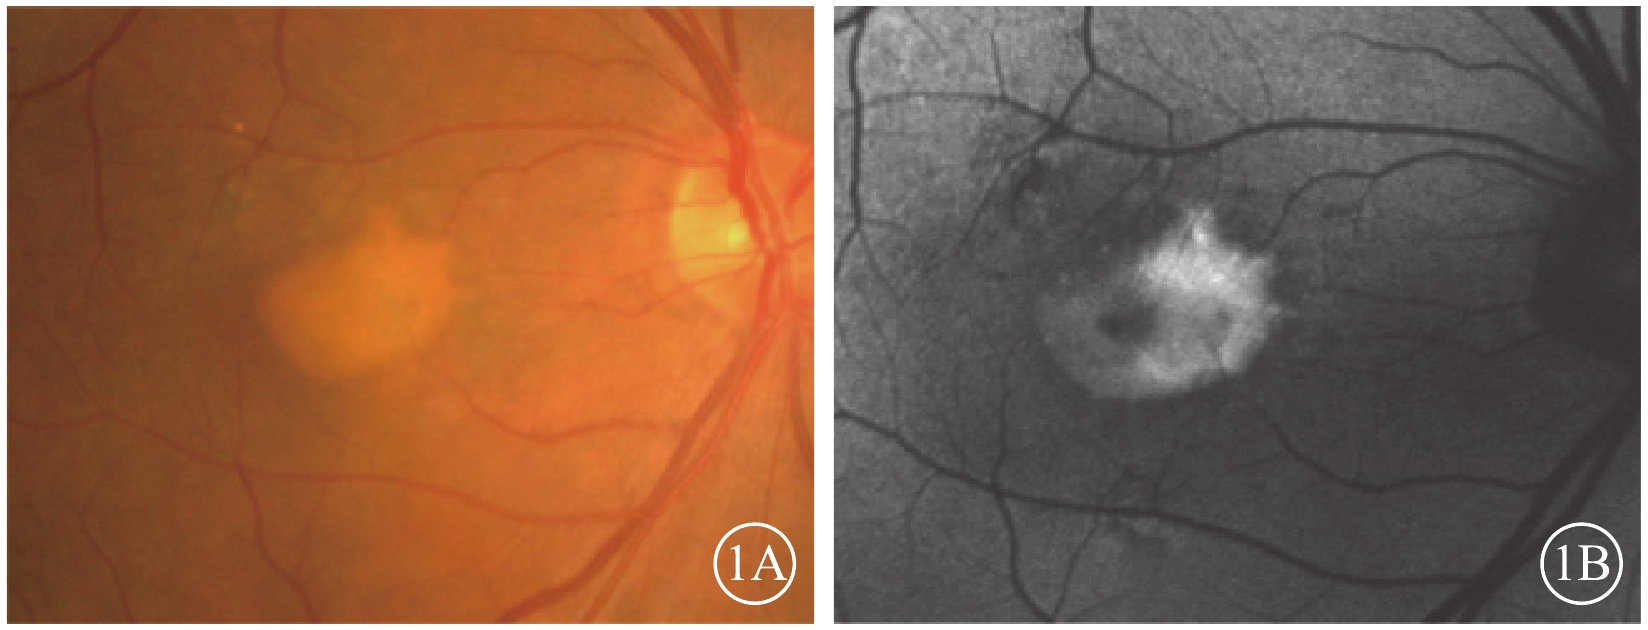

眼底彩色照相檢查發現,所有患眼黃斑區視網膜下可見一邊界清晰的黃白色病灶(圖1A),黃斑區終末血管爬行于病灶之上。黃白色病灶密度并不完全一致,部分區域病變較為濃密,部分則較為稀薄。病灶內部及周圍未見出血、滲出。病灶周圍可見小片狀色素脫失(圖1A)。其余部分視網膜、視神經、血管均未見異常。

FAF檢查發現,所有患眼均可見與彩色眼底像中病灶一致的強自身熒光。病灶內自身熒光強度不一(圖1B),彩色眼底像中較為稀薄的區域呈相對弱自身熒光,較為濃密的區域呈強自身熒光。與彩色眼底像對應的小片狀色素脫失區域可見弱自身熒光(圖1B)。

圖1

AOFVD患眼彩色眼底、FAF像。1A. 彩色眼底像,黃斑區視網膜下可見邊界清晰的黃白色病灶,病灶周圍可見小片狀色素脫失;1B. FAF像。與彩色眼底像對應的病灶處可見強自身熒光,病灶內自身熒光強度不一;與彩色眼底像對應的小片狀色素脫失區域可見弱自身熒光

圖1

AOFVD患眼彩色眼底、FAF像。1A. 彩色眼底像,黃斑區視網膜下可見邊界清晰的黃白色病灶,病灶周圍可見小片狀色素脫失;1B. FAF像。與彩色眼底像對應的病灶處可見強自身熒光,病灶內自身熒光強度不一;與彩色眼底像對應的小片狀色素脫失區域可見弱自身熒光

眼底彩色照相檢查發現,所有患眼黃斑區視網膜下可見一邊界清晰的黃白色病灶(圖1A),黃斑區終末血管爬行于病灶之上。黃白色病灶密度并不完全一致,部分區域病變較為濃密,部分則較為稀薄。病灶內部及周圍未見出血、滲出。病灶周圍可見小片狀色素脫失(圖1A)。其余部分視網膜、視神經、血管均未見異常。

FAF檢查發現,所有患眼均可見與彩色眼底像中病灶一致的強自身熒光。病灶內自身熒光強度不一(圖1B),彩色眼底像中較為稀薄的區域呈相對弱自身熒光,較為濃密的區域呈強自身熒光。與彩色眼底像對應的小片狀色素脫失區域可見弱自身熒光(圖1B)。

圖1

AOFVD患眼彩色眼底、FAF像。1A. 彩色眼底像,黃斑區視網膜下可見邊界清晰的黃白色病灶,病灶周圍可見小片狀色素脫失;1B. FAF像。與彩色眼底像對應的病灶處可見強自身熒光,病灶內自身熒光強度不一;與彩色眼底像對應的小片狀色素脫失區域可見弱自身熒光

圖1

AOFVD患眼彩色眼底、FAF像。1A. 彩色眼底像,黃斑區視網膜下可見邊界清晰的黃白色病灶,病灶周圍可見小片狀色素脫失;1B. FAF像。與彩色眼底像對應的病灶處可見強自身熒光,病灶內自身熒光強度不一;與彩色眼底像對應的小片狀色素脫失區域可見弱自身熒光